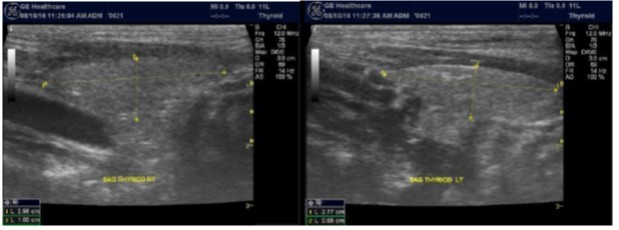

In our study many patients were found to have nodules look very much like PT adenoma, Figure 7 below. At least, 4 patients were subsequently confirmed to have parathyroid adenomas, Figure 8 and 2 patients underwent surgery

Despite the fact that nodular pathology was found to be very prevalent among our study population, it has been found difficult to differentiate between thyroid and parathyroid pathology using ultrasound alone. However, some characteristics of the parathyroid glands might suggest parathyroid pathology in the context of the clinical picture of secondary or tertiary hyperparathyroidism which is very prevalent in ESKD patients’ populations.

Figure 7.Thyroid nodule suspicious for Parathyroid adenoma due to its location

Figure 8.Nodule that proven to be a parathyroid adenoma, volume =5265 mm3

There are 4 parathyroid glands (2 superior, 2 inferior) imbedded within the thyroid gland. The parathyroid glands are bean-like shape and small (20-40 mg) 25. Sonographically, the parathyroid glands have the following features 25:

Hyperplastic glands: hypoechoic, volume <500 mm3.

Nodular glands: hypoechoic. Volume >500 mm3

Histologically, if the excised gland has volume <500 mm3 it is said to be hyperplastic and if the volume is more than 500 mm3 it is nodular hyperplasia in 80% of cases26. In secondary HPT, the increase in the volume of parathyroid glands is associated with increase in vascularity, as evident in Color Doppler imaging 27.